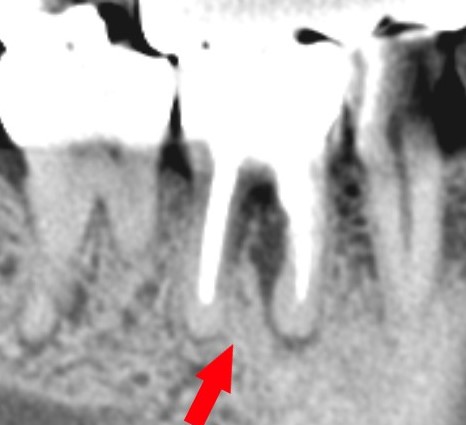

短い根管充填のデンタルレントゲン写真

根管充填が短く、やり直しが必要です。

レントゲン写真(CT像)ですぐ分かります。

デンタルレントゲン上で見える根管充填の不足部分

根管充填が短い部分は、上の赤い部分です。

赤矢印は、化膿で骨が溶けている部分です。